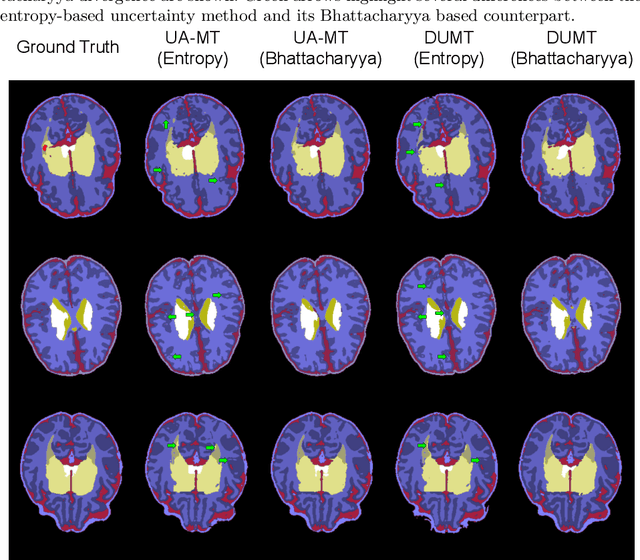

Abstract:Semi-supervised learning has emerged as an appealing strategy to train deep models with limited supervision. Most prior literature under this learning paradigm resorts to dual-based architectures, typically composed of a teacher-student duple. To drive the learning of the student, many of these models leverage the aleatoric uncertainty derived from the entropy of the predictions. While this has shown to work well in a binary scenario, we demonstrate in this work that this strategy leads to suboptimal results in a multi-class context, a more realistic and challenging setting. We argue, indeed, that these approaches underperform due to the erroneous uncertainty approximations in the presence of inter-class overlap. Furthermore, we propose an alternative solution to compute the uncertainty in a multi-class setting, based on divergence distances and which account for inter-class overlap. We evaluate the proposed solution on a challenging multi-class segmentation dataset and in two well-known uncertainty-based segmentation methods. The reported results demonstrate that by simply replacing the mechanism used to compute the uncertainty, our proposed solution brings substantial improvement on tested setups.